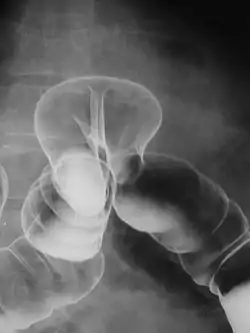

Сульфат барію, нерозчинний у воді білий порошок, використовується для посилення контрастності візуалізації органів шлунково-кишкового тракту. Залежно від способу і цілей введення, сульфат барію змішують з водою, з загущувачами і ароматизаторами. У зв'язку з тим, що ця речовина нерозчинна в воді, готовий контрастний препарат являє собою непрозору білу суміш. Використовується для перорального застосування або введення за допомогою клізми. Виводиться з організму з фекаліями.